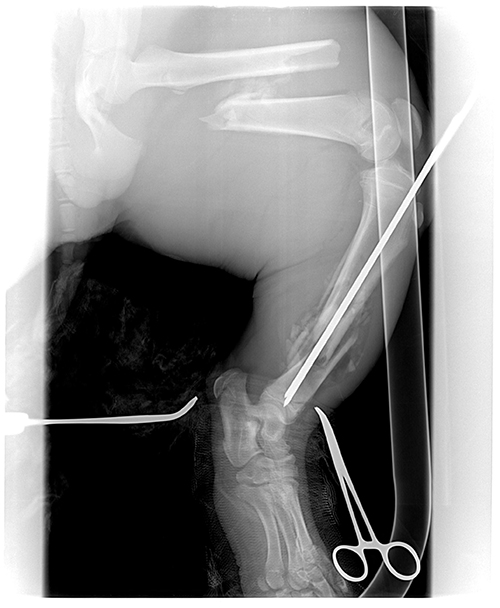

By day 14 our veterinarian felt he was strong enough to set his leg. Both large bones in his left hind leg were badly broken (see pictures above). The operation took almost five hours. She put rods through the center of the bones. It was a very big job, but everything went well.

On Jan. 1, 2013, Frank’s veterinarian X-rayed his leg again to see if it had healed properly and to see if the rods needed to be removed. She was very happy with how the leg had healed. She needed to remove only one of the rods. Frank now had only 30 days more to heal from having the rod removed and then he would be able to move in with the girls.